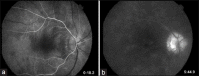

Birdshot retinochoroidopathy (BSRC) is an uncommon, but well-characterized chronic, bilateral posterior uveitis, which is uniquely associated with the human leukocyte antigen-A29 phenotype. The disease presents predominantly in middle-aged Caucasian females who complain of blurred vision, floaters, photopsias, paracentral scotomas and nyctalopia. While autoimmune mechanisms are thought to play an important role in the pathogenesis of BSRC, its etiology remains unknown. Important questions remain in our understanding of BSRC with respect to its pathogenesis, epidemiology, optimal treatment, and prognosis, including the determinants of remission and relapse, as well as the best strategy for monitoring disease activity, progression and response to therapy with electroretinographic and psychophysical testing, established and emerging imaging modalities, and peripheral cytokines profiles.